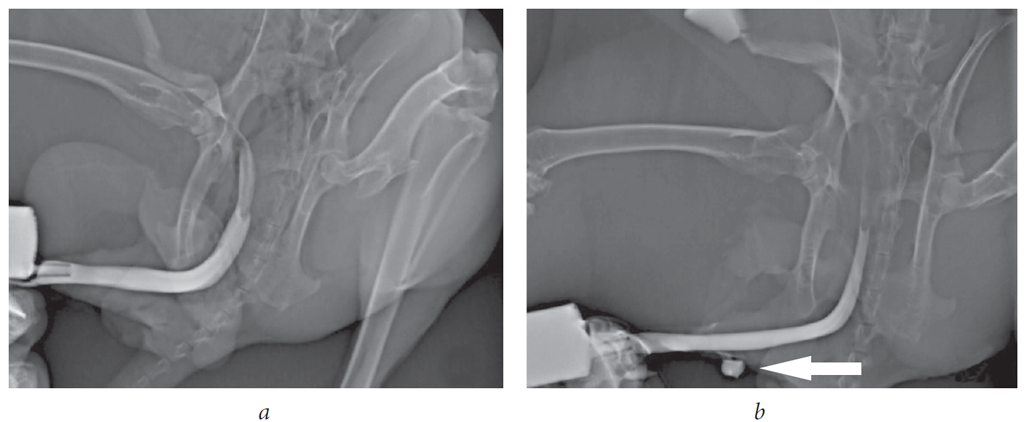

При макроскопической оценке зоны имплантации ни в одной группе не было выявлено отторжения имплантата, сужений и дивертикулов уретры (рис. 7).

Рис. 7. Макропрепараты уретры кролика: a — визуализация зоны имплантации тканеинженерной конструкции (группа 1); b — зона имплантации не визуализирована (группа 2); c — визуализация буккального графта; d — уретро-кожный свищ (стрелка)

Fig. 7. Macro preparations of the rabbit urethra: a – visualization of the TEC implantation zone (group 1); b – the TEC implantation zone is not visualized (group 2); c – visualization of the buccal graft; d – urethrocutaneous fistula (arrow)

В 1-й и 2-й группах через 1 и 2 мес. после хирургического вмешательства у всех кроликов визуализировали зону имплантации (рис. 7, а). Однако через 3 мес. в 1-й и 2-й группах зона имплантации была визуализирована в 66,7 и 88,9 % соответственно (рис. 7, b). Буккальный графт отчетливо визуализировался у всех животных (рис. 7, c). Два ранее описанных уретро-кожных свища выявлены в группе кроликов, которым были имплантированы ТИК на основе ПЛГ + ПЛК с клетками буккального эпителия (рис. 7, d). При статистическом анализе, значимой корреляции между имплантированными материалами и возможностью формирования свищевого хода не выявлено (уровень значимости p точного критерия Фишера при межгрупповом сравнении > 0,05).